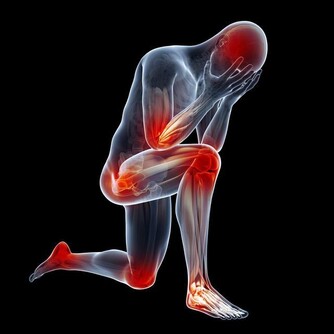

4、積極運動,量力而行

糖尿病病人最適宜的運動是散步,打羽毛球、登山也是不錯的選擇。